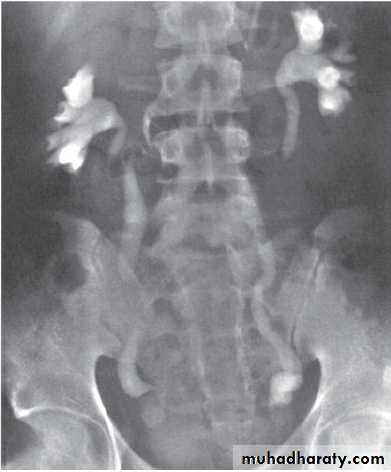

The VCUG:

the definitive examination

to diagnose and grade reflux and establish reversible causes

must include a voiding phase:

in some cases, reflux may be seen only during the elevated intravesical pressures associated with micturition.

in visualizing the urethra, may allow the diagnosis of outflow obstruction to be made (e.g., posterior urethral valves).

DMSA scan to detect and monitor associated renal cortical scarring.

The intravenous urography (IVU) findings are usually normal in lower grades of reflux.

MCUG